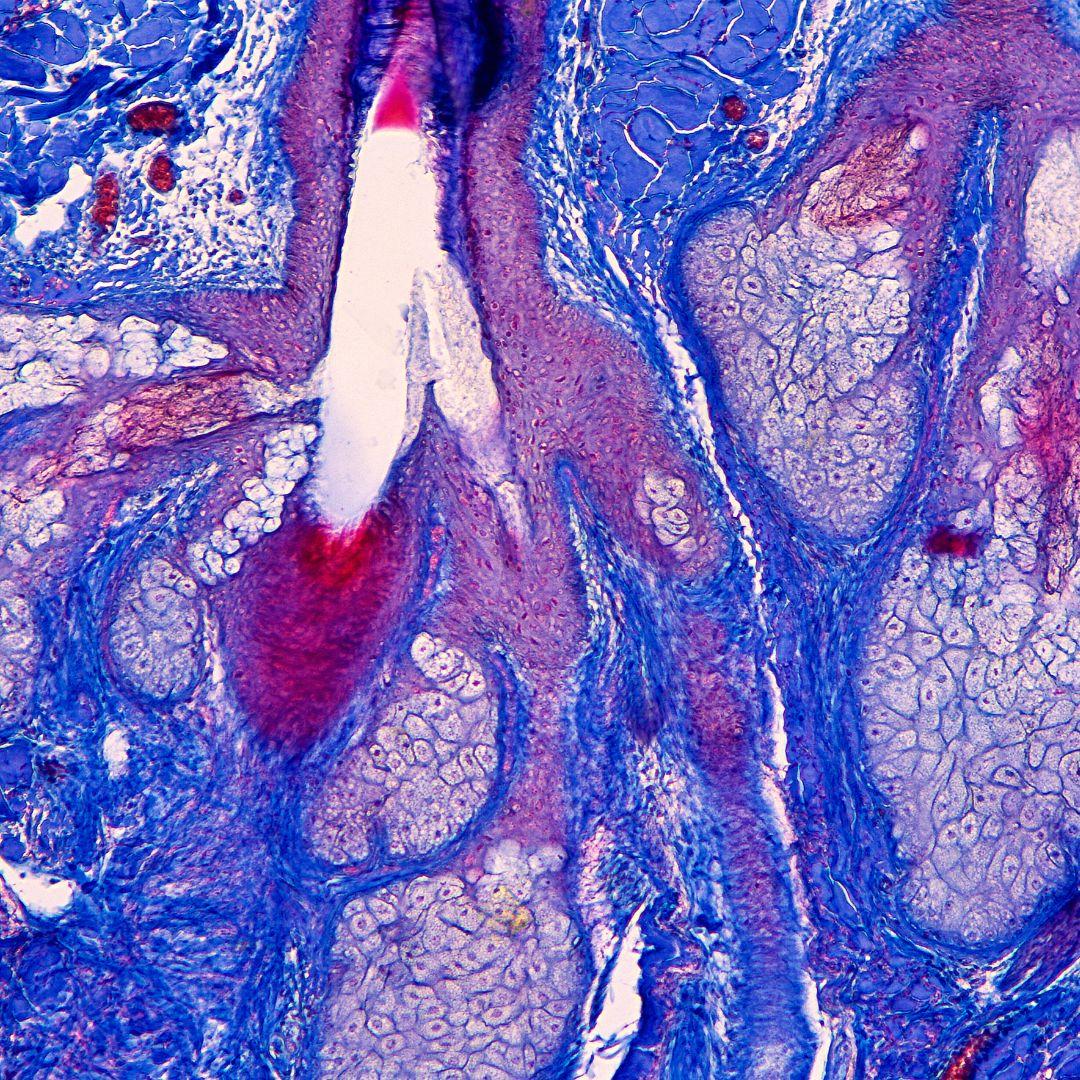

La couche supérieure de la peau, appelée épiderme, est composée de cellules mortes appelées kératinocytes. Ces cellules sont produites dans les couches profondes de l’épiderme et remontent vers la surface, où elles sont éliminées et remplacées par de nouvelles cellules. Les kératinocytes contiennent de la kératine, une protéine solide qui donne à la peau sa résistance et sa souplesse.

La couche intermédiaire de la peau, appelée derme, est composée de fibres de collagène et d’élastine, qui confèrent à la peau sa résistance et sa capacité d’élasticité. La derme contient également des vaisseaux sanguins, des nerfs, des glandes et des follicules pileux.

La couche inférieure de la peau, appelée hypoderme, est composée de cellules graisseuses qui sont responsables de l’isolation thermique et de la protection mécanique de la peau. L’hypoderme contient également des vaisseaux lymphatiques et des nerfs qui assurent la sensation tactile et la régulation de la température corporelle.